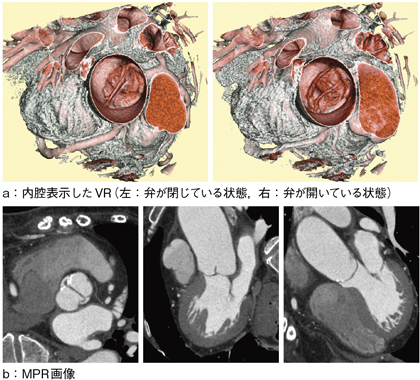

図5は,大動脈弁が2尖弁であった症例である。紙面では,二次元表示しかできないために表現が難しいが,こういった症例では,4Dで観察できるように画像提供を行っている。VirtualPlaceには,超高速画像処理エンジン「FORMULA」が搭載されており,画像処理枚数が多くなる心臓CTにおいてもストレスなく画像処理を行うことが可能である。

図5 大動脈弁が2尖弁の症例

VRでは,内腔表示することで大動脈弁を観察しやすくなる。